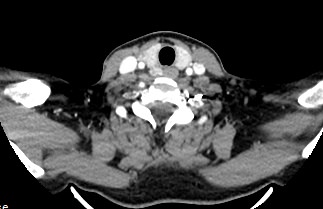

КТ щитовидной железы часто используется в диагностике доброкачественных и злокачественных опухолей железы, оценки распространенности процесса, поэтому для улучшения визуализации патологических очагов дополнительно применяется внутривенное болюсное контрастирование. Методика контрастирования позволяет увидеть на снимке опухоли минимальных размеров за счет того, что контраст избирательно накапливается в измененных тканях и обеспечивает яркое изображение патологического очага на фоне здоровых окружающих тканей.  Контрастирование дает возможность определить врачу границы опухоли, ее размеры, степень васкуляризации, точное расположение, особенно это важно при нетипичной (загрудинной) локализации органа.

В наших центрах обследование щитовидной железы выполняется на современных мультиспиральных томографах TOSHIBA AQUILION, оснащенных увеличенным количеством сверхчувствительных детекторов, позволяющих производить множество срезов с минимальной толщиной от 0,5 мм. Инновационные возможности аппаратов обеспечивают получение множества послойных снимков высокого качества и построение на их основе трехмерной модели органа. Кроме того, аппаратура позволяет за счет сокращения времени сканирования минимизировать лучевую нагрузку на пациента.

Мультиспиральная компьютерная томография позволяет точно определить размеры и расположение щитовидной железы, выявить опухолевые образования, оценить их структуру, степень кровоснабжения, взаимодействие с окружающими тканями.